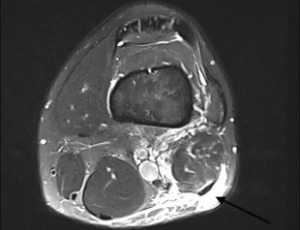

Nonoperative Management of Distal Biceps Femoris Avulsion in a Professional Soccer Player

A 24-year-old professional soccer player sustained a rare distal biceps femoris avulsion injury during a training session, characterized by a near-complete tear at the musculotendinous junction approximately 5 cm proximal to the fibular head, without tendon detachment or significant retraction. Given the unusual nature of this injury and the absence of tendon retraction or involvement of lateral stabilizing structures, a conservative, nonoperative treatment approach was adopted.

J Phys Med Rehabil, 2025, Volume 7, Issue 1, p106-112 | DOI: 10.33696/rehabilitation.7.052